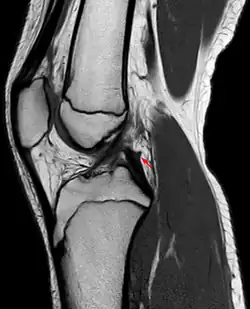

Posterior meniscofemoral ligament on MRI, sagittal -